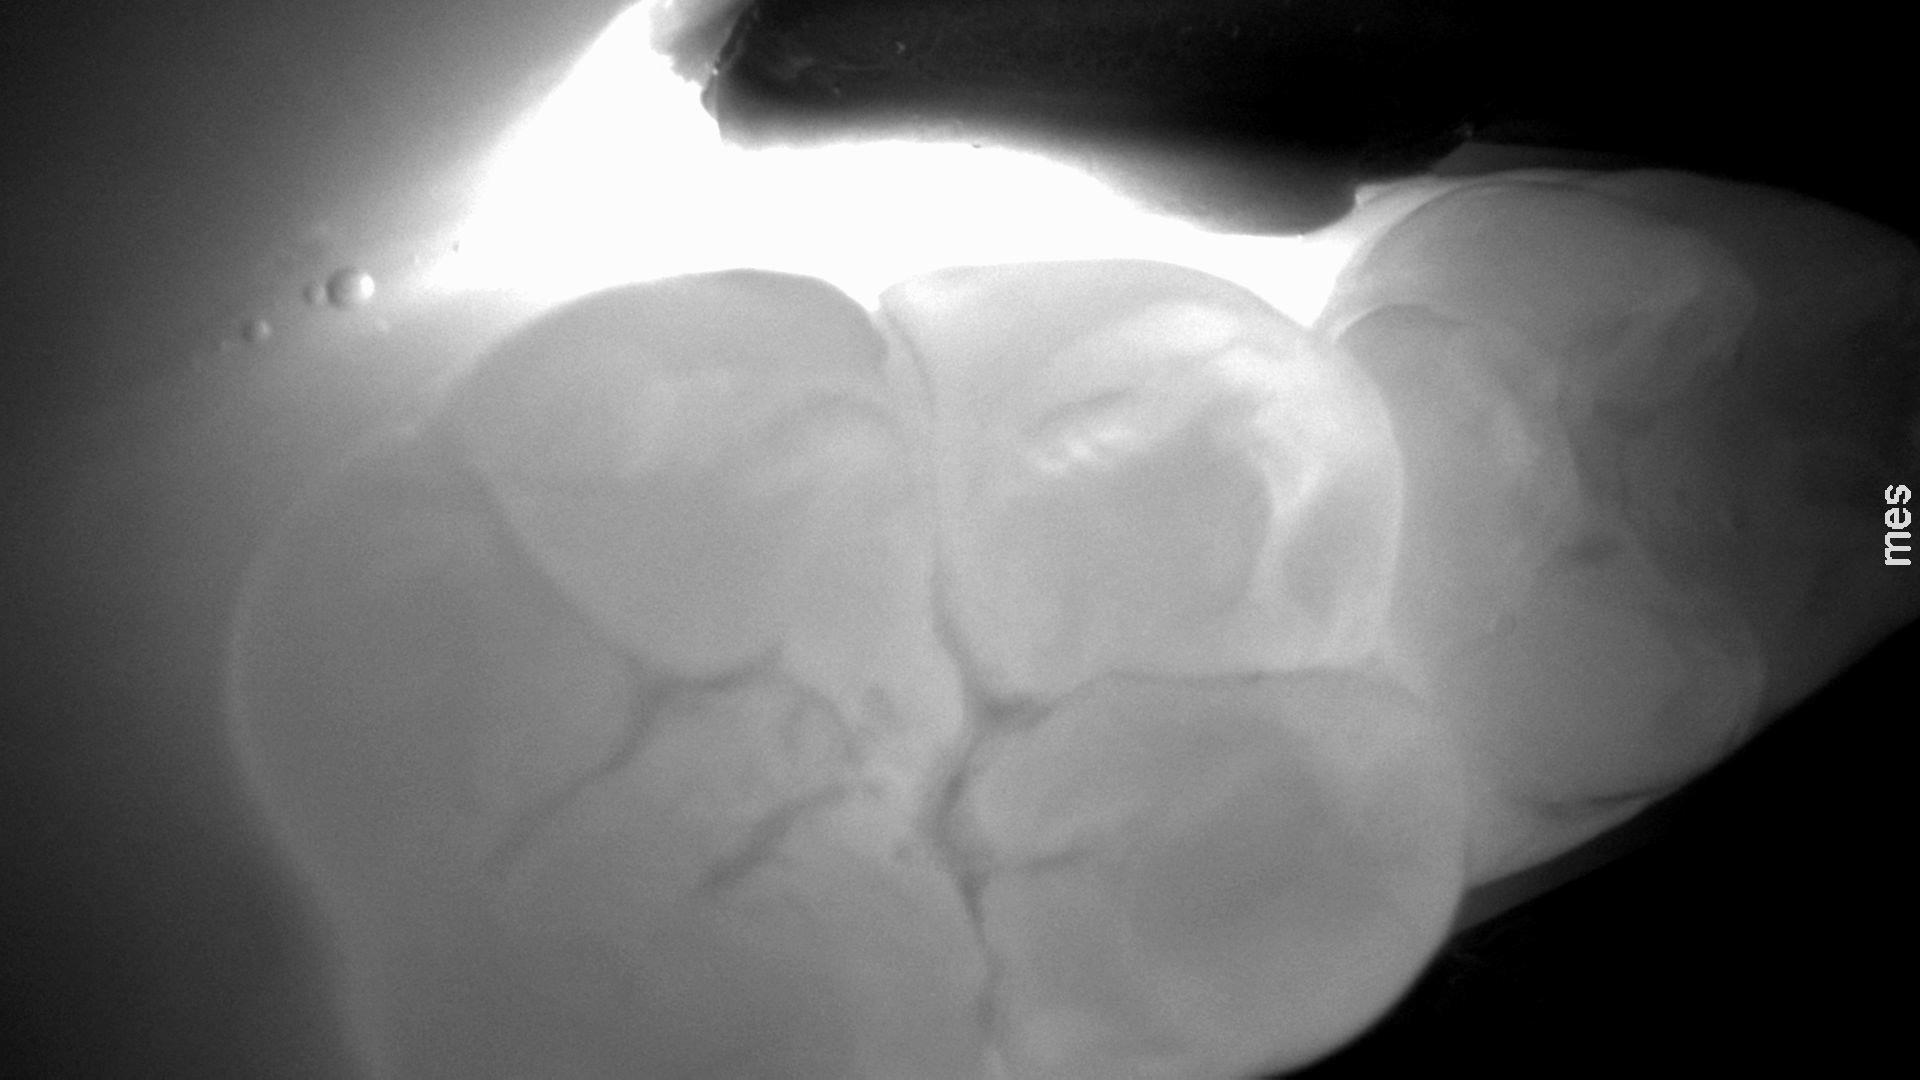

Obraz prześwietlonego zęba trzonowego ze zmianą próchnicową na powierzchni okluzyjnej uzyskany w technologii NILT przy pomocy urządzenia DIAGNOcam (KaVo).

Zdjęcie lub film z badania danego zęba jest analizowane przez lekarza dentystę w poszukiwaniu wszelkich zaciemnień powierzchni, które będą wskazywać na obecność zmiany próchnicowej. Na powierzchni okluzyjnej będą to nieregularne plamy, zlokalizowane najczęściej w okolicy bruzd zębów, wykazujące penetrację próchnicy pod szkliwo. Na powierzchniach stycznych będą to ciemne miejsca w kształcie trójkątnym lub trapezowym, szerszą ścianą skierowane w stronę zewnętrznej powierzchni szkliwa, a węższą ścianą (w przypadku trapezu) lub ostrym kątem (w przypadku trójkąta) w stronę zębiny, lub wręcz stykającą się z obrysem zębiny. Im szerszy jest kontakt tej ciemnej powierzchni z obrysem zębiny tym bardziej zaawansowany jest ubytek próchnicowy na powierzchni stycznej.